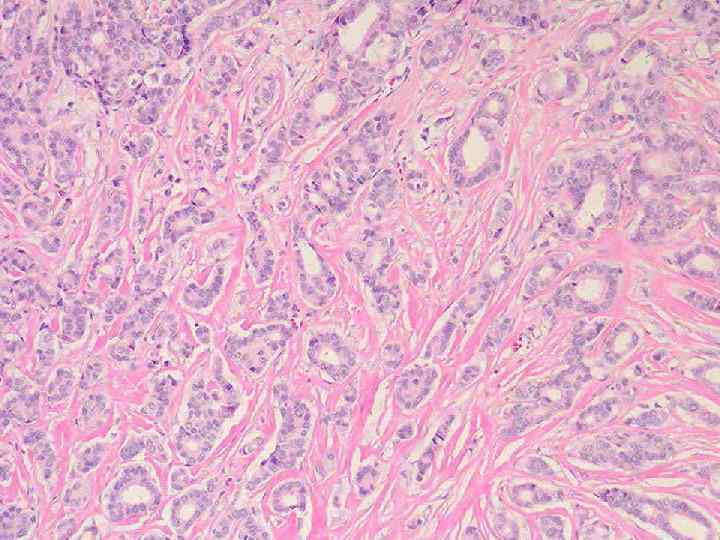

Аномалии молочной железы: медицинские примеры и визуализация

Раздел: Мудрость в деталях